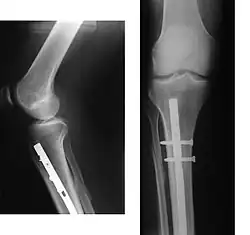

Эндопротезирование коленного сустава

При наличии показаний к операции методом выбора может быть эндопротезирование суставов. В настоящее время разработаны и успешно применяются эндопротезы тазобедренного и коленного суставов. При остеопорозе эндопротезирование осуществляется конструкциями с цементным креплением. Дальнейшее консервативное лечение коленного сустава способствует снижению сроков реабилитации оперированных больных и повышению эффективности лечения.